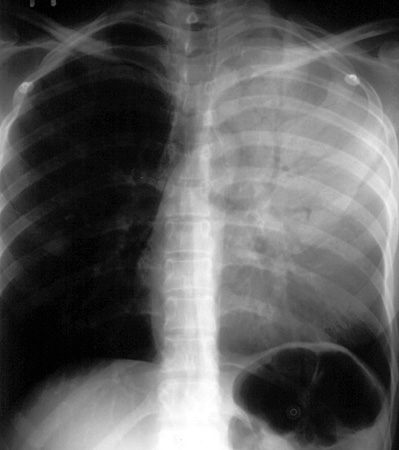

Left Upper Lobe Consolidation